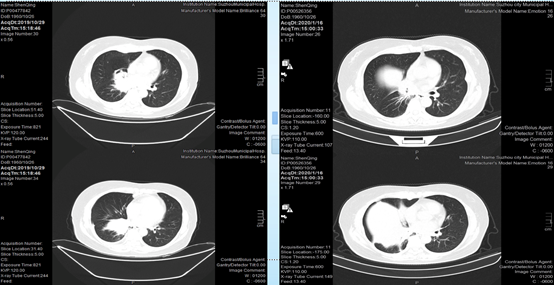

2020-01-16,CT复查提示患者胸膜处结节较前缩小,右下肺病灶较前缩小。

2020-03-23,患者再次复查CT,发现胸膜下结节较前增大,右下肺病灶继续缩小,但患者胸腔积液明显增多,疗效评估疾病进展(PD)。

2020-05-07,患者复查过程中,发现胸腔积液进一步增多,胸膜下病灶进一步增大。随即调整治疗方案,予以奥希替尼80mg qd,再次胸腔闭式引流,胸水送检制作细胞蜡块,胸腔内注射恩度,予培美曲塞、卡铂化疗2周期。

2020-08-03,患者再次入院复查,发现胸膜下病灶较前缩小,胸腔积液也有一定好转,但持续存在。

2020-09-16,CT复查提示患者胸水进一步增多。

2020-10-27,CT复查提示患者胸水较前稍有减少,但仍持续存在。